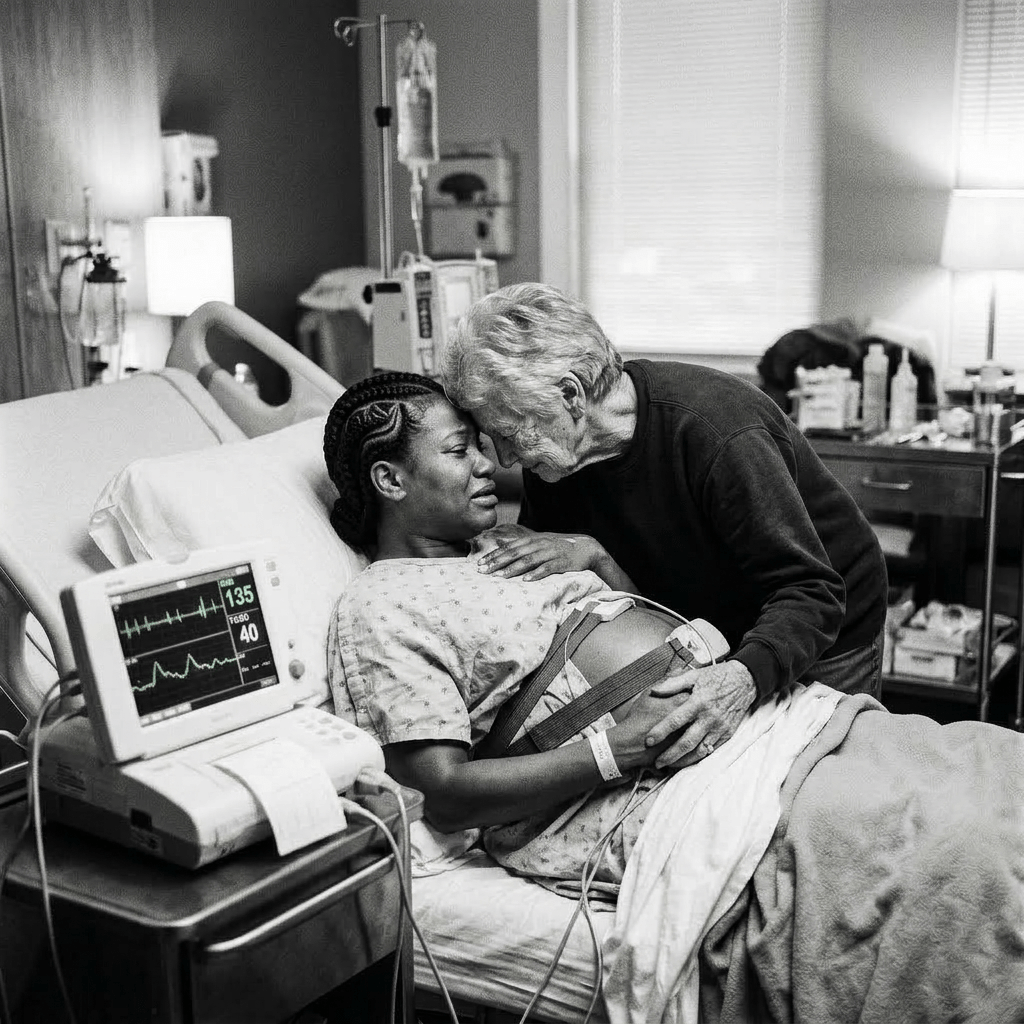

Ik begeleid ergens in een nachtdienst Zola. Een jonge vrouw uit Eritrea ze bevalt van haar eerste kindje. Het is een zwangerschap die is ontstaan uit trauma en geweld. Alleen in Nederland, ver weg van alles wat vertrouwd was, vindt ze steun bij Lida, een vrijwilliger bij het COA die als een moederfiguur aan haar zijde staat.

Zola is kwetsbaar, gelukkig is de natuur mild voor haar. Maar de bevalling vraagt niet alleen fysieke kracht, maar ook een enorme mentale strijd. Met zachte begeleiding, geduld en onvoorwaardelijke nabijheid van Lida ontstaat er minimaal vertrouwen.

Wanneer haar dochter wordt geboren, volgt er eerst afstand. Maar ook een voorzichtig begin. In een breekbaar en ontroerend moment maakt Zola, op haar eigen manier, contact met haar kind.